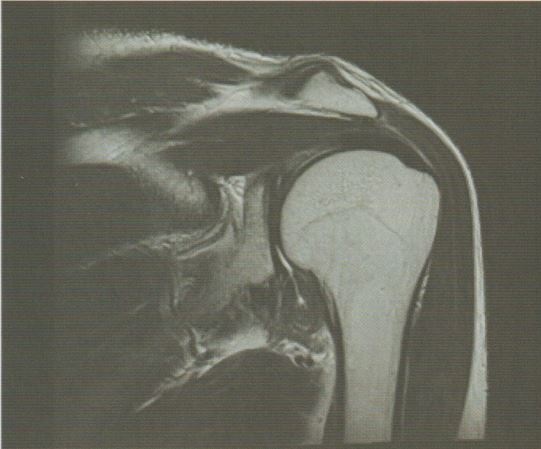

정상적인 어깨 관절과 오십견(동결견)의 상태를 비교해보면, 관절낭이 두꺼워지고 손상이 발생하며 서로 들러붙는 현상이 나타납니다. 이로 인해 관절 내부 공간이 줄어들고 움직임 장애가 발생하게 됩니다.

오십견(동결견, 유착성 관절낭염)의 관절 내부 치료 지점입니다.